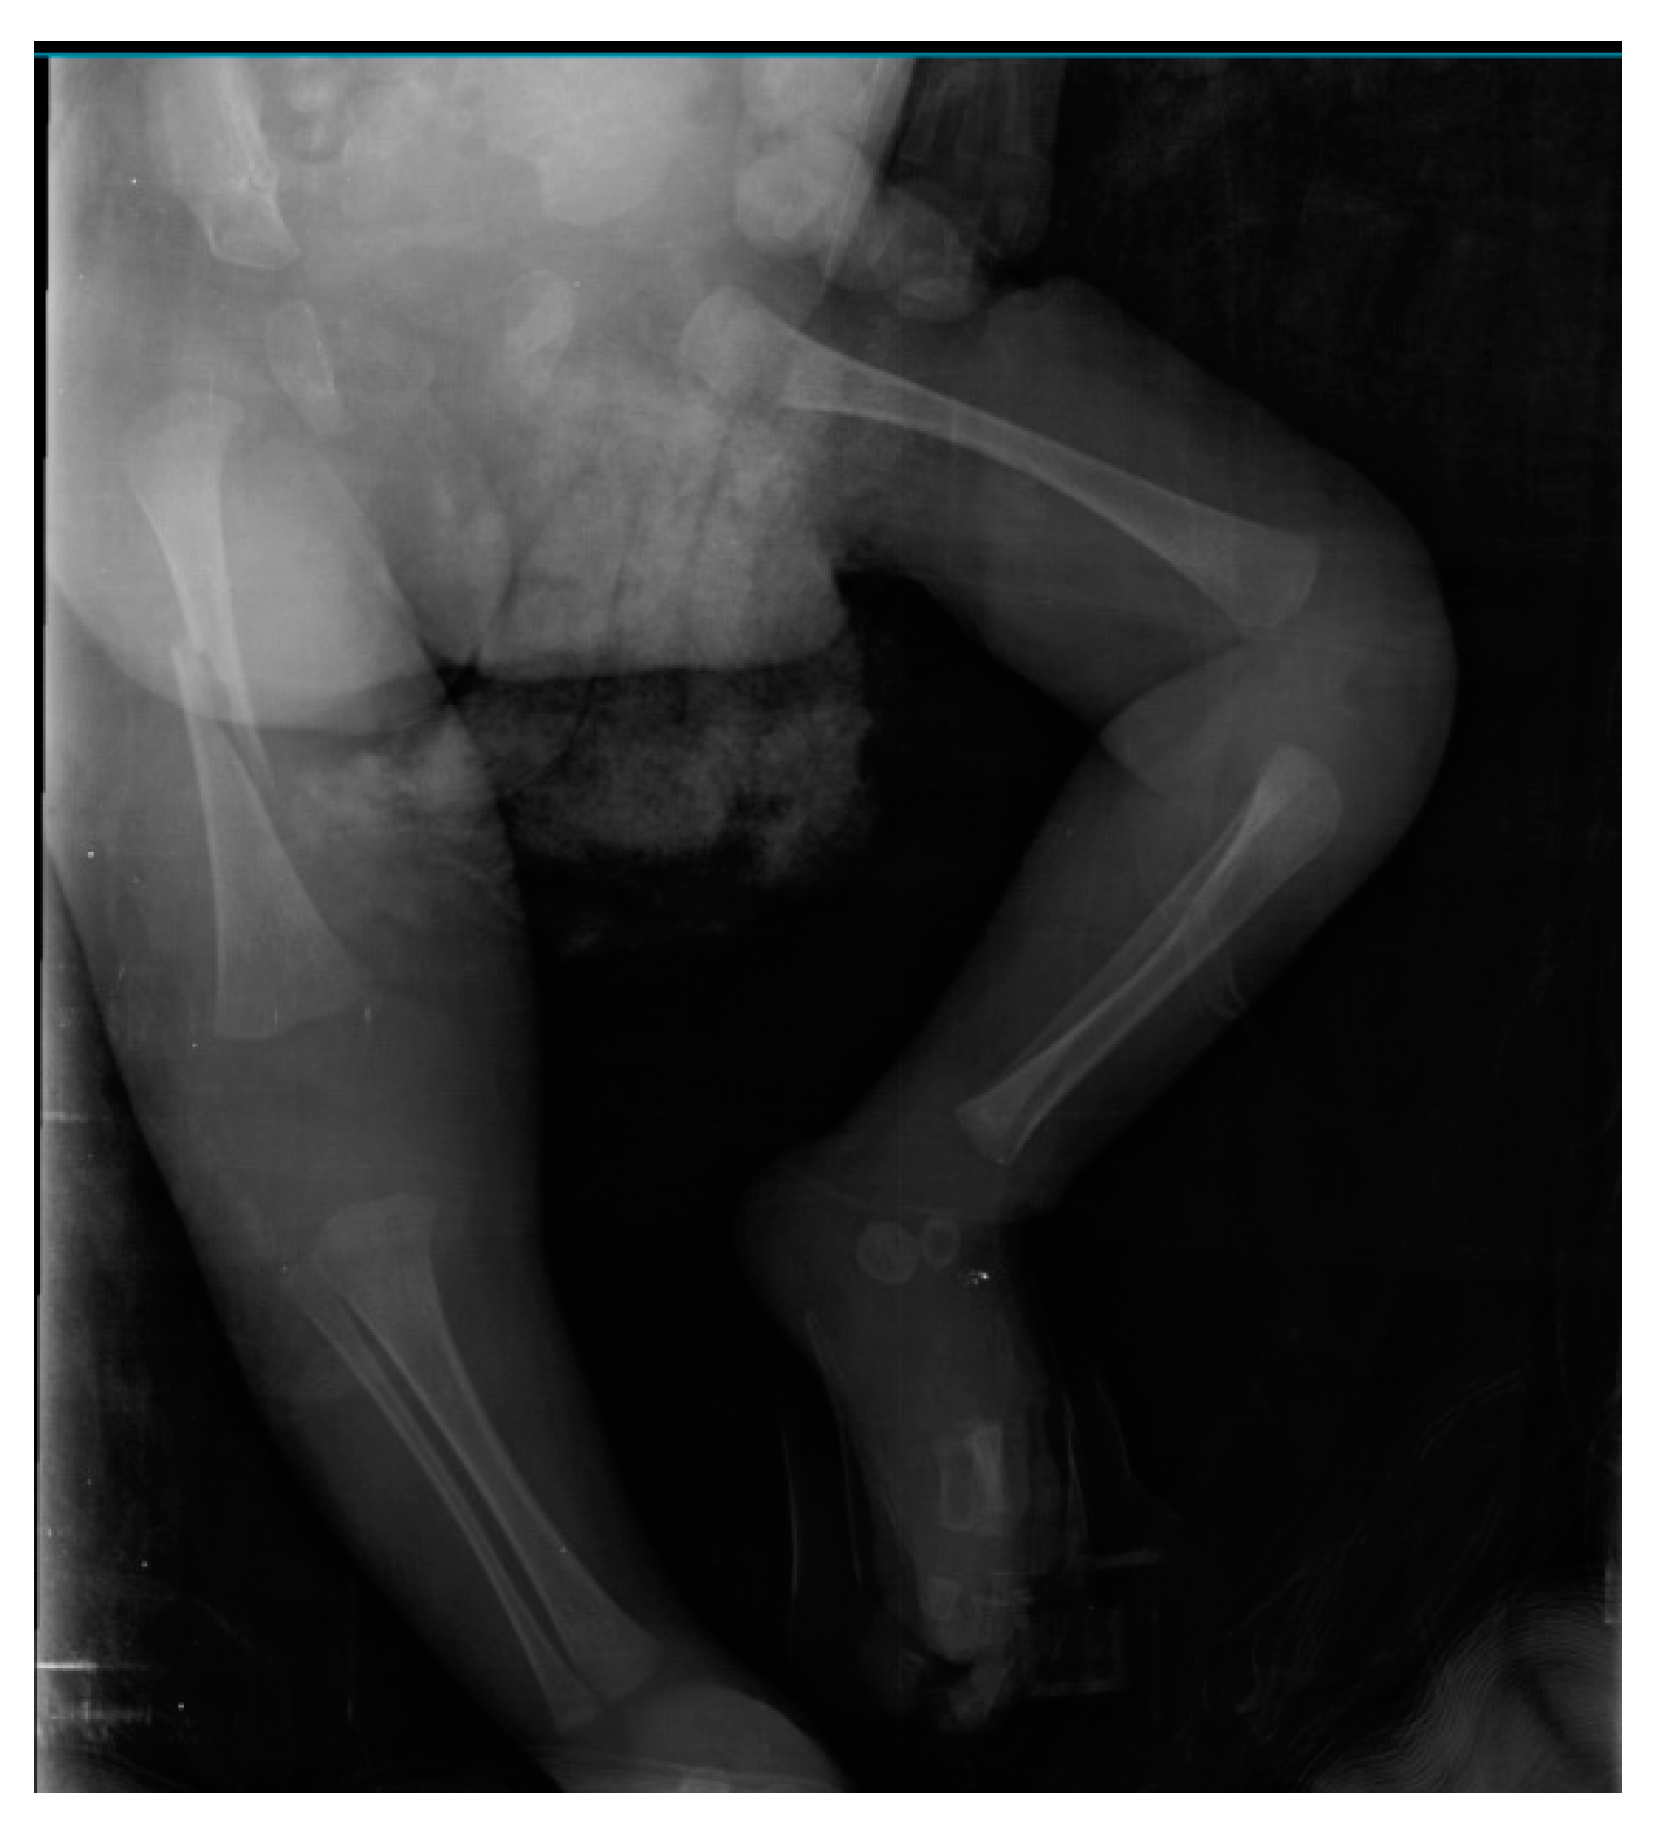

An Unusual Case of Neonatal Hypotonia and Femur Fracture: Neuromuscular Variant of Glycogen Storage Disease Type IV

2. Case

2.1. Initial Presentation